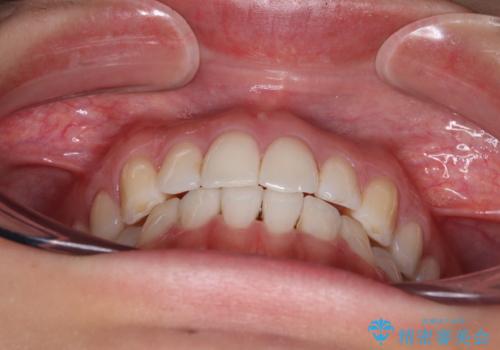

前歯の重なりをインビザライン・モデレートで矯正治療

- 上下前歯の重なりを気にして来院された患者様です。

安価なインビザラインパッケージを用いての治療を希望されており、デコボコの程度が中等度であったため、インビザライン・モデレートを用いて矯正治療を行うこととしました。